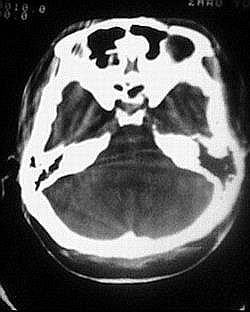

患者/49y/ 女/4年前有脑梗, 现因右侧肢体无力来院做ct扫描 ! 老师们看看这骨头有事吗?钙化点是什么原因呀??

1.颅骨对称性、形态规整性增厚,应属发育异常。四叠体池左后侧单发点状钙化,无其他阳性表现,多属正常,不需要过多关注。

除了以上大家关注到的,我发现左侧鼓室、鼓窦扩大有骨质破坏,考虑有慢性中耳炎肉芽肿形成

2.颅骨内外板广泛性增厚,板障狭窄甚至消失,双侧对称。无明显相应临床症状。考虑“泛发性骨皮质增厚症”。可进一步检查下颌骨及管状骨骨干。(下颌骨骨小梁增多、密集,密度增高亦为本病特点,管状骨骨干皮质向内增厚引起骨皮质厚度增加,骨密度增浓、髓腔狭窄但不消失,骨干周径较少增加)。与石骨症鉴别,后者很少影响颅盖骨和下颌骨,管状骨改变主要累及干骺端和骨骺,而骨干皮质较少增厚,椎体和髂骨翼有特征性表现。